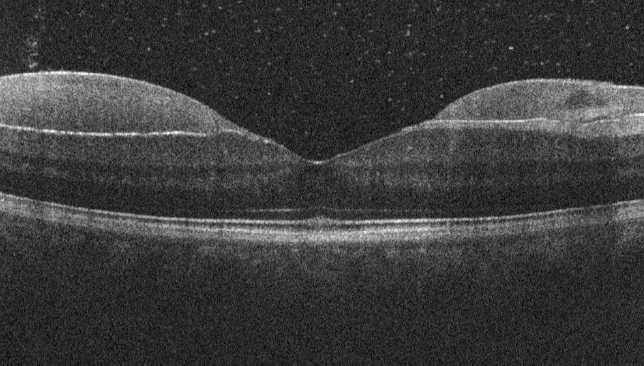

<p>Figure 3. At 1 month, the patient's fundus examination was unremarkable.</p>

Figure 3. At 1 month, the patient's fundus examination was unremarkable.

Observation was recommended. At the 1-month follow-up visit, the fundus appearance had returned to normal, with mild residual inferior vitreous hemorrhage (Figure 3) and VA of 20/16 OD.